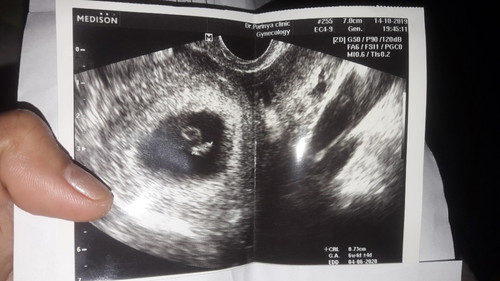

ซาวตอนอายุครรภ์6w4dค่ะ

ในรูปใบซาว มีตรงไหนบอกมั้ยค่ะว่าหัวลูกเต้น วันที่ไปหาหมอ ปวดท้อง เลยลืมถามค่ะ

น้องตัวเล็กอยู่เลยยังไม่ชัดหรอก